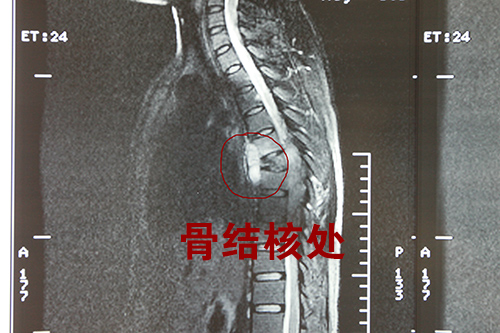

7月1日上午,我院骨一科收治了一位特殊的患者,患者年仅24岁,已经怀孕5个月,于6月24 日开始无明显诱因出现胸骨疼痛伴双下肢麻木,两天前双下肢瘫痪,当时即被送往南昌某医院治疗,磁共振提示:胸5-8椎体骨质破坏,并椎旁和椎管内脓肿形成,胸6-9层面脊髓受压,家属被告知患者无恢复可能。

怀揣最后一丝希望,家属推着患者来到我院,慕名找到骨一科熊龙博士,熊龙博士收治患者后在第一时间进行了全科讨论,考虑患者已经瘫痪,熊龙博士认为手术指征明确,应拟急诊手术,此方案经详细讨论后最终确立。由于患者已有5个月身孕,所以手术存在巨大风险,虽然患者及家属均同意终止妊娠,但假如手术失败,患者仍旧瘫痪,更有可能导致终身不孕,熊龙博士在准备手术方案时异常谨慎,经过精心完善的术前准备,患者入院后第二天便在全麻下行了“胸椎后路病灶清除+植骨内固定术”,经过几个小时的紧张手术,顺利完成,术后熊龙博士也为患者制定了详细的治疗方案和肢体的康复锻炼计划,术后患者情况良好,双下肢已恢复感觉并能渐渐进行运动。